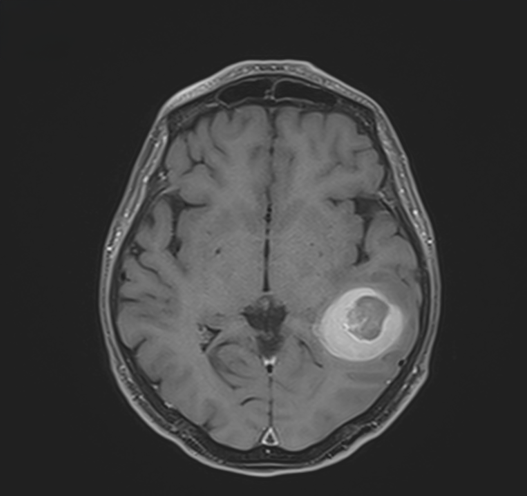

cavernome temporal

Figure 1. Cavernome temporal ayant saigné, en pré-opératoire